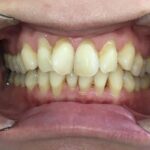

とてもきれいな歯並びになり、お母様もご本人様も大変満足されていました。

現在は歯並びをキープさせる「保定期間」に入っており、永久歯が完全に生え揃うまで今後は経過を見ていきます。